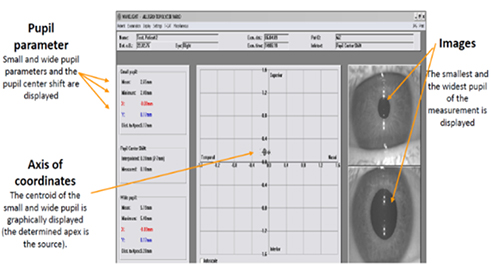

또한 빛의 밝기 변화에 따른 동공 중심 이동과 홍채에 관한 정보를 파악, 수술 시 정확한 시축 중심을 맞춤으로써 다이내믹한 눈의 변화를 반영한 정교한 수술이 가능합니다.